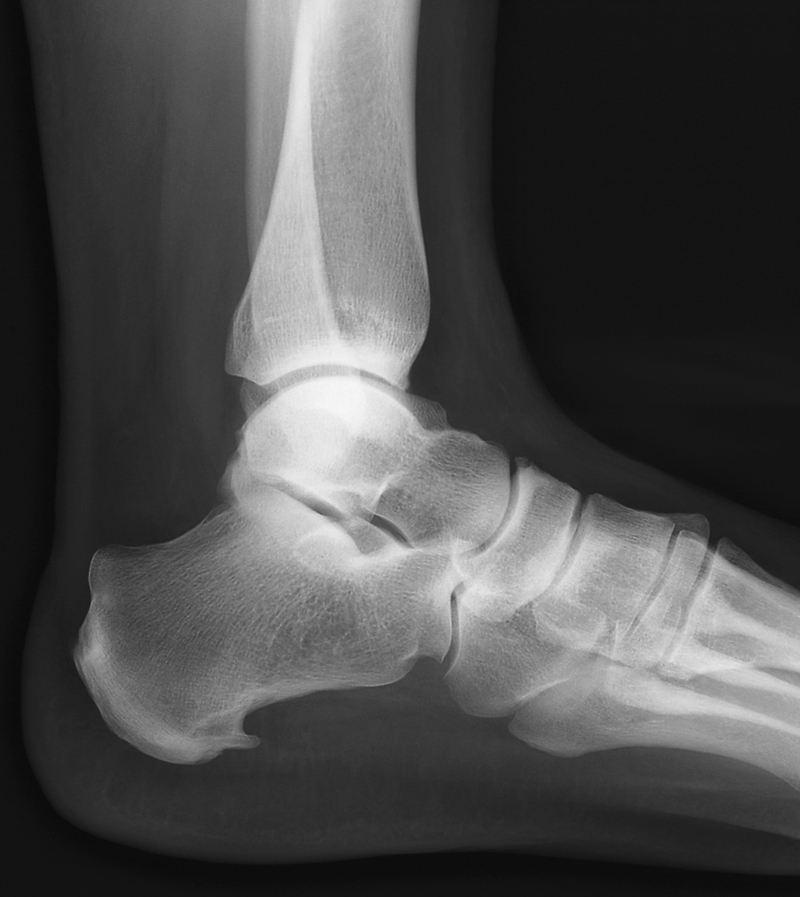

Bác sĩ sẽ dùng X-quang để xác định có gai xương gót hay không. Nhưng kích thước của gai xương gót không quyết định cường độ đau, triệu chứng đau. Bởi vì có nhiều trường hợp không có gai xương gót trên phim X-quang vẫn đau. Hoặc ngược lại đã điều trị hết đau nhưng vẫn còn gai xương gót. Có trường hợp gai rất to nhưng người bệnh lại không cảm thấy đau gì cả, chỉ khi đi kiểm tra mới vô tình phát hiện ra có gai xương gót.

Gai xương gót: Nguyên nhân, triệu chứng và cách điều trị 2

Hình ảnh gai xương gót trên phim X quang